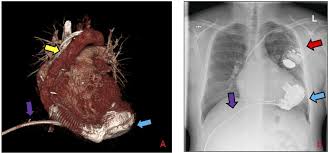

Implantable Left Ventricular Assist Device Indications Eligibility And Current Outcomes Heart

Implantable Left Ventricular Assist Device Indications Eligibility And Current Outcomes Heart from heart.bmj.com